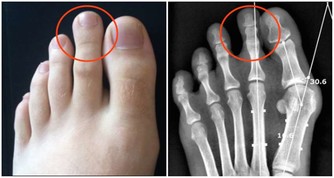

7.下半身出現腫脹

如果你發現臀部及以下部位腫脹,這也很可能是甲狀腺疾病的症狀,這是由於體內液體滯留在此處,於是出現水腫。